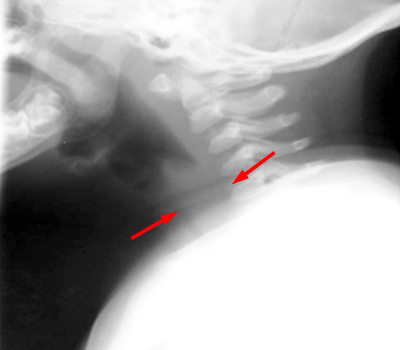

A lateral soft tissue radiograph will show the AP narrowing of the subglottic trachea, which normally should maintain the same AP diameter to the thoracic inlet. An AP soft tissue neck film will also show subglottic narrowing, but this can be confused with normal respiration changes. CXR will usually show signs of the viral bronchitis. Most importantly, the radiographic examination will also determine if there is a retropharyngeal abscess or an airway foreign body.

AP and lateral soft tissue exam of the neck demonstrates the subglottic edema.

Note that the epiglottis is not thickened as in epiglottitis.